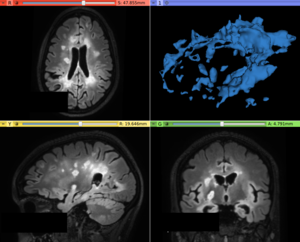

This extension provides image segmentation and local image contrast enhancement approaches in order to detect abnormal white matter voxels signals in magnetic resonance images. At moment, there are available the LS Segmenter (specific for hyperintense Multiple Sclerosis lesion segmentation on T2-FLAIR images), LS Contrast Enhancement (specific to increase the contrast of abnormal voxels of T2-FLAIR images) and AFT Segmenter as a simple implementation of a recent automatic Multiple Sclerosis (MS) lesion segmentation[1] approaches. The LS Segmenter module implements a T2-FLAIR hyperintense lesion segmentation based on the algorithm published in the paper[2].